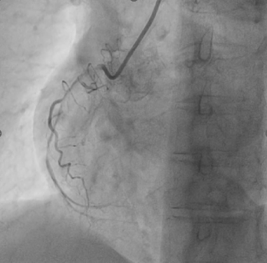

Pre-dilationwith 1.5x15mm compliant balloon. (Balloon didn’t go beyond this point).Changed to workhorse wire insidemicrocatheter by trapping the wire. Coronary dissection NHLBI- Type D/F seenwith reduced antegrade flow

2.0x12mmcompliant balloon didn’t cross proximal RCA, dilated at 10 atmand it ruptured.

Pre-dilationwith 1.5x15mm compliant balloon. (Balloon didn’t go beyond this point).Changed to workhorse wire insidemicrocatheter by trapping the wire. Coronary dissection NHLBI- Type D/F seenwith reduced antegrade flow

2.0x12mmcompliant balloon didn’t cross proximal RCA, dilated at 10 atmand it ruptured.